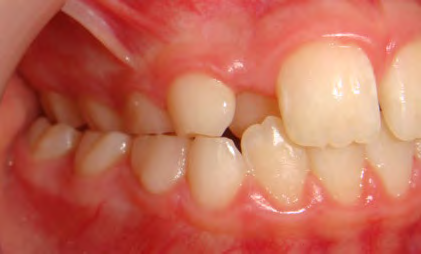

All of the patients below had been told they required extractions by orthodontists, some insisting that they could not be treated without extractions.

They were all treated without extractions, head gear or facemasks at Vakresmil and represent just a small sample of cases treated between 2004–2014.

The patient below had severe crowding of both upper canines and the lower right 5. The upper 4’s and 2’s were actually in contact.